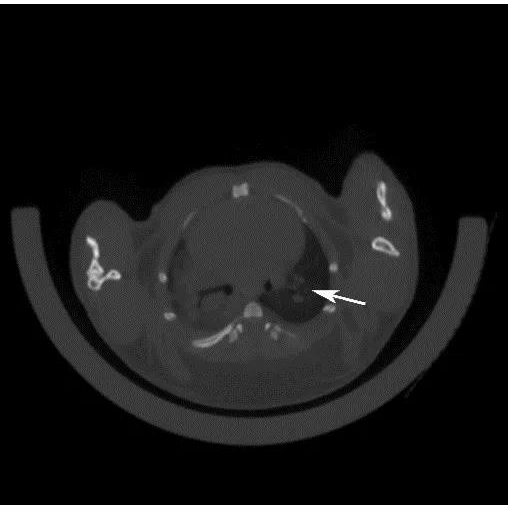

目前國(guó)際上應(yīng)用最廣泛的肺癌動(dòng)物模型就是Kras-LSL-G12D小鼠模型,可以通過與肺上皮細(xì)胞特異性的Cre轉(zhuǎn)基因小鼠雜交來實(shí)現(xiàn)Kras突變體的激活,從而導(dǎo)致肺癌的發(fā)生。南模生物提供的Kras(LSL-G12D/+)小鼠品系在Kras突變基因的上游插入了loxp-stop-loxp終止序列,其在沒有cre重組酶的條件下是不表達(dá)的。Cre介導(dǎo)的重組可去除終止密碼子,使致癌基因表達(dá)。采用腺病毒載體攜帶Cre感染肺部細(xì)胞后,導(dǎo)致肺腫瘤發(fā)生的頻率非常高(圖8)。

圖9 采用氣管內(nèi)注射的方法,將AAV-cre病毒注射到小鼠肺部,3個(gè)月后對(duì)小鼠肺部進(jìn)行CT檢測(cè),CT結(jié)果顯示有明顯的腫瘤的形成。